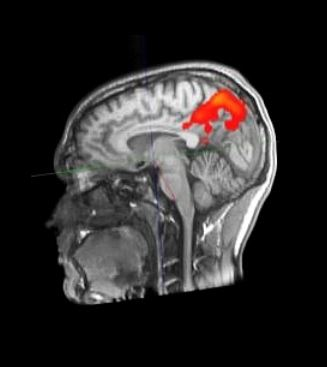

With the help of new methods of neuroscience, the abilities of our brain can be examined more and more precisely. A look inside the brain is possible with imaging methods such as computed tomography (CT) or magnetic resonance imaging (MRI). Functional magnetic resonance imaging (fMRI) can reveal changes in blood flow in brain areas and thus not only structure but also activation. In this way, the neural network in the brain is indirectly recorded in its operation. In this way, it is hoped to better understand how our brain works and learns. However, the knowledge gained so far about how the brain works during learning is very limited due to various methodological limitations, so this topic remains a major challenge for brain research.

fMRT Picture of a 24 year old - https://de.wikipedia.org/wiki/Funktionelle_Magnetresonanztomographie#/media/Datei:Aktivitaethinten.jpg